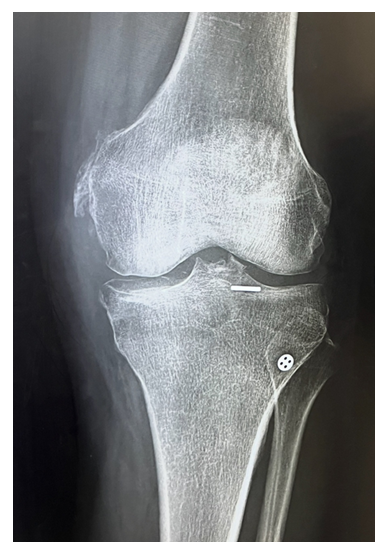

Due to the increased risk of thromboembolism, an inferior vena cava (IVC) filter was placed preoperatively. Surgical management was performed the following day under general anesthesia. An anterolateral portal was created, and superolateral outflow was established. A longitudinal incision was made, and soft tissue and hematoma were cleared using cautery and shaver to expose the fracture site. With the knee in flexion, an arthroscopic grasper was used to reduce the fracture fragment. An ACL drill guide was positioned to maintain the reduction. Arthroscopic visualization confirmed successful reduction, and a guide wire was inserted into the ACL footprint. A 4 mm reamer was used to create a tunnel through which a TightRope device was passed to secure the fracture. The implant was engaged, and with application of tension, the fracture remained stable. Fluoroscopic imaging confirmed secure engagement of the button with the ACL fibers and successful flipping of the button. Final reduction was verified under imaging, and the wound was closed with Monocryl and Dermabond.

Postoperative management included knee immobilization and physical therapy for mobilization with an assistive device as needed. DVT prophylaxis was continued under the guidance of the primary care provider.